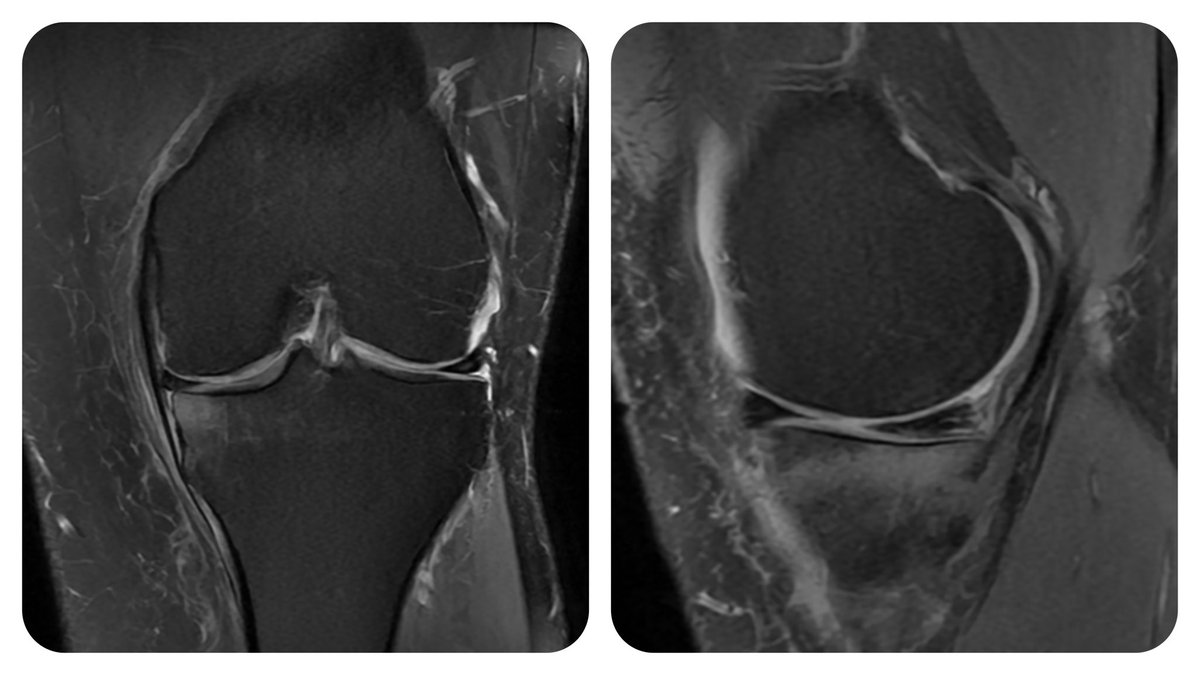

47yo, medial knee pain BMI 41.5 He lives in 🇺🇸 3 ortho there recommended UKA None talked about weight loss and exercise WHAAAAAAT?? 🤯🤯🤯

47yo, medial knee pain

BMI 41.5

He lives in 🇺🇸

3 ortho there recommended UKA

None talked about weight loss and exercise

WHAAAAAAT?? 🤯🤯🤯